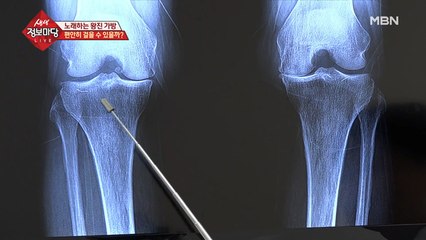

척추기형까지 발견된 상황, 어머니는 다시 걸을 수 있을까…?